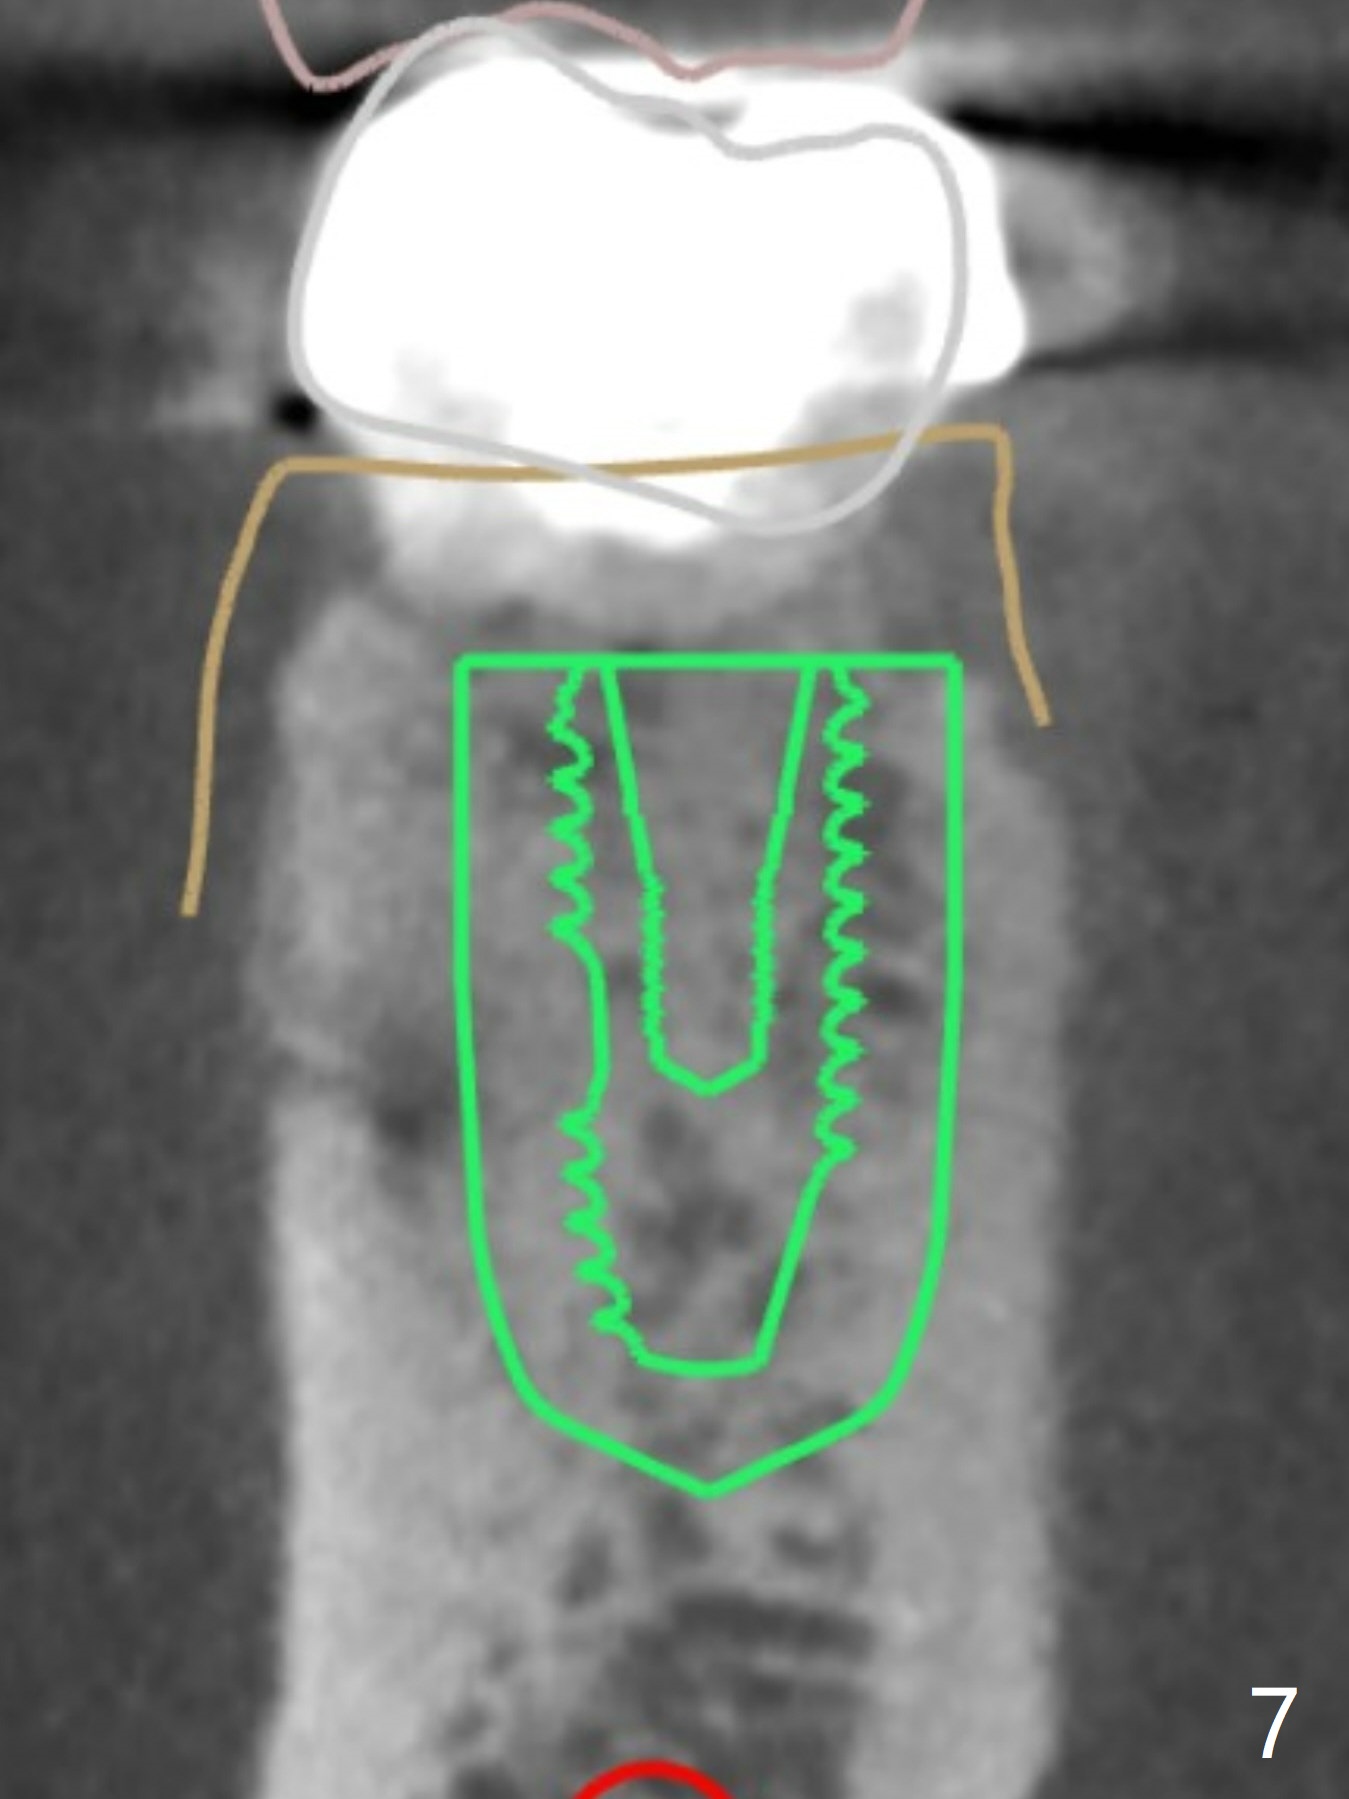

A 54-year-old man decides to extract the tooth #19 because of failure of RCT in the disto-lingual long curved root. Since it is difficult to drill through the roots, the latter will be removed. Use 2.2 mm drill to reach the depth first, look for deviation and take PA. Prepare cowhorn, surgical handpiece and proximators. PRFx1. Use 4.5x11.5 mm drill before placing 5.5x11mm IBS implant.